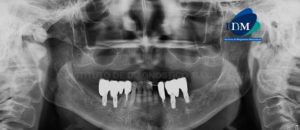

Paciente femenino de 55 años de edad, es referido al Instituto de Diagnóstico Maxilofacial (IDM) para evaluación integral. En la radiografía panorámica (Figura 1) se

Paciente masculino, 62 años de edad, acude al Instituto de Diagnóstico Maxilofacial (IDM)- Sede Surco, para evaluación dentaria. En la radiografía panorámica (Figura 1) se